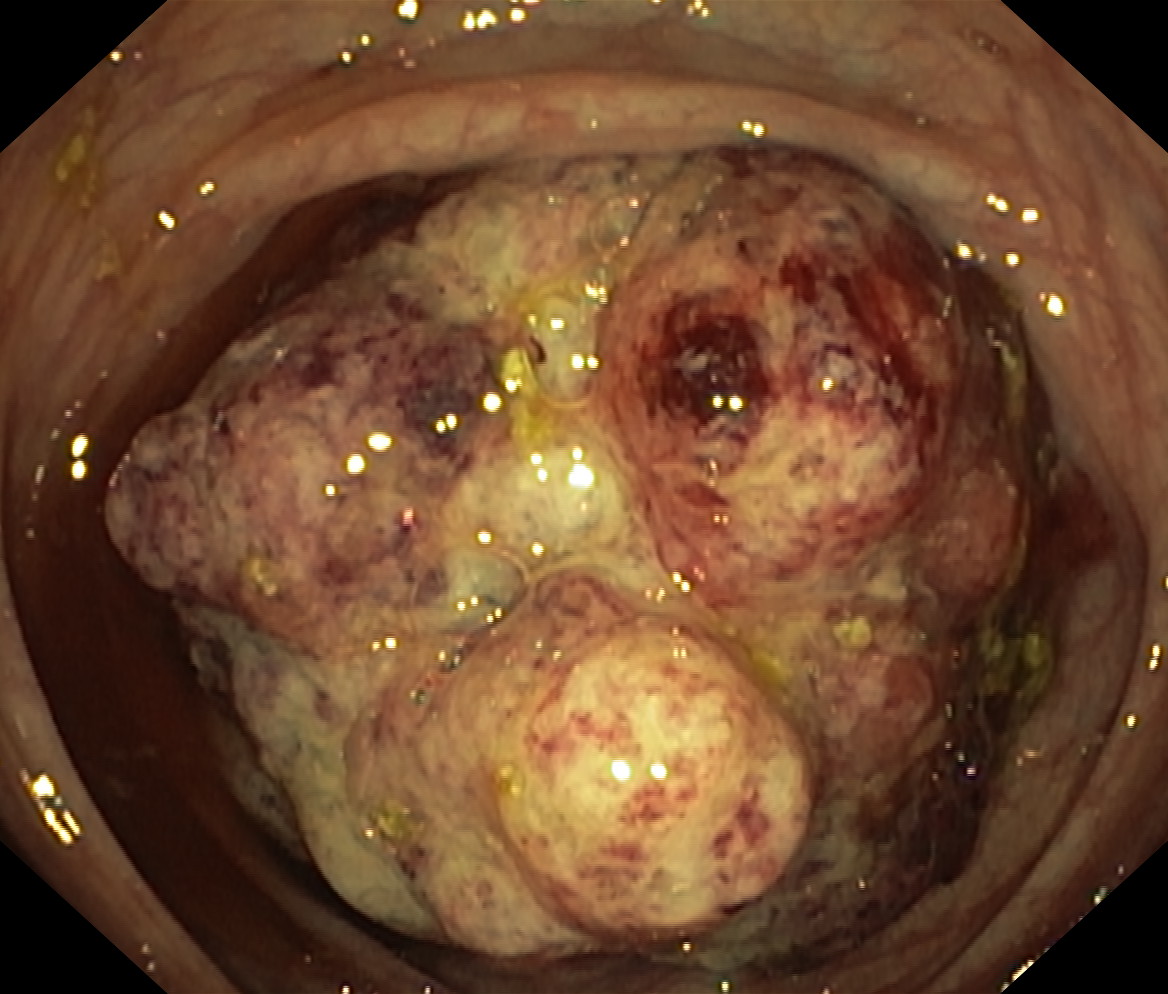

Nowotwory przewodu pokarmowego